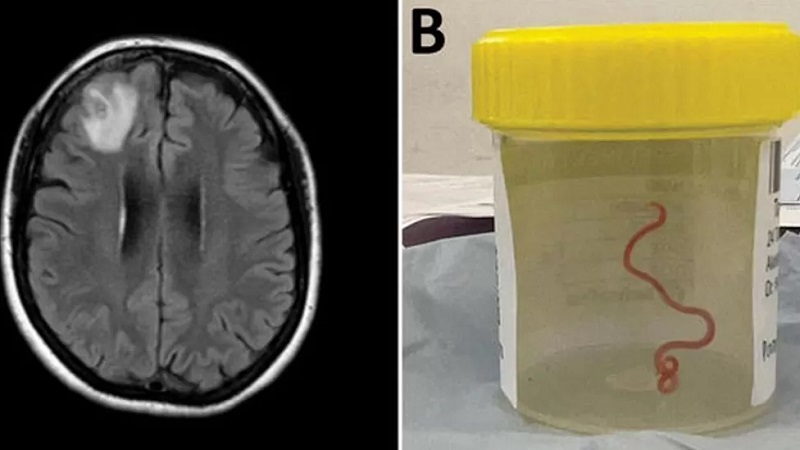

विश्वमै पहिलो पटक मानिसको मस्तिष्कमा ८ सेन्टिमिटर